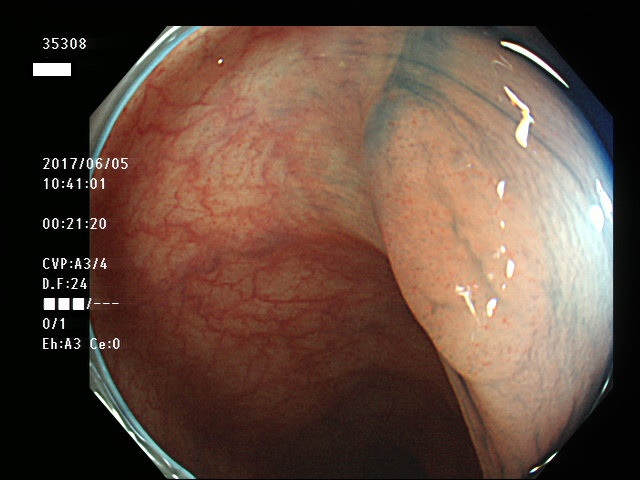

上記100名より抽出した平坦・陥凹型腺腫・SSAP(=癌化の危険が高いが見落としやすい病変)の内視鏡写真